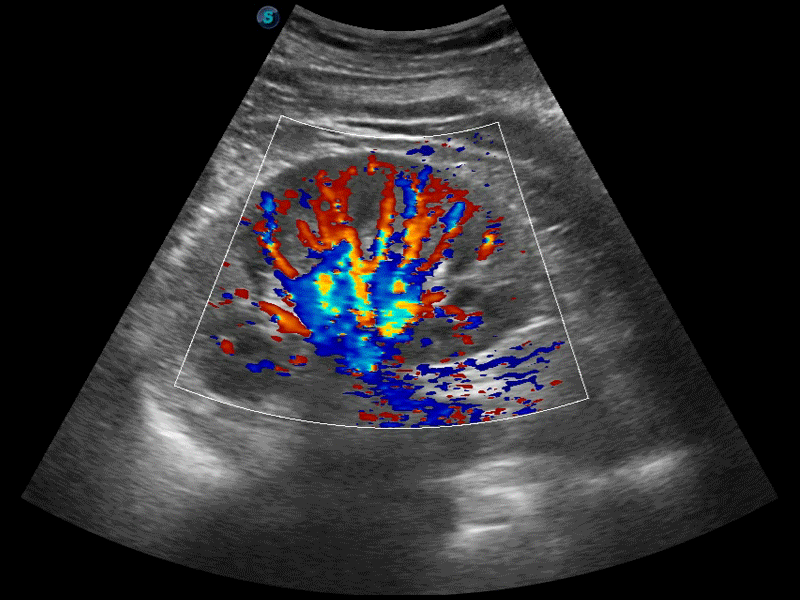

高分辨率血流成像技術(shù)提高了對低速血流信號的檢測能力。在提高空間分辨率的同時,也克服了血流外溢現(xiàn)象,為用戶提供更加真實的血流動力學(xué)信息。